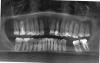

nekamon Опубликовано 3 февраля, 2013 Поделиться Опубликовано 3 февраля, 2013 (изменено) Здравствуйте! Подскажите пожалуйста, по этому КТ (Галлилеос), могу ли я обойтись без наращивания костной ткани ипоставить себе имплантант на верхнюю челюсть? Ссылка на просмотрщик:http://yadi.sk/d/ULK09GyB2Jv1T Ссылка на файлы КТ:http://yadi.sk/d/0PLUFDiw2JvJr Изменено 3 февраля, 2013 пользователем nekamon Ссылка на комментарий